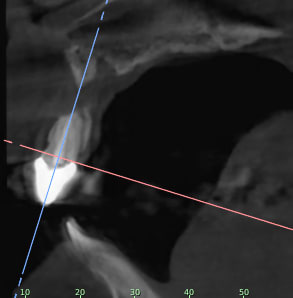

Je rajoutes quelques coupes et une rétro... C'est vraiment un massacre à la tronçonneuse!

C1 yphslc - Eugenol

C2 zxqv4g - Eugenol

C3 eyq9c9 - Eugenol

C4 nbfjjy - Eugenol

C5 tbh27p - Eugenol

C6 hpnjso - Eugenol

C7 wstgml - Eugenol

C8 zrgdkv - Eugenol

C9 l71h8s - Eugenol

C10 llgubu - Eugenol

C11 xl426v - Eugenol

24/04/2019 à 15h19

D'autres coupes et une rétro

2 ozhekl - Eugenol

3 r9cfdm - Eugenol

1 skjekn - Eugenol

Rétro24042019 sngvhg - Eugenol